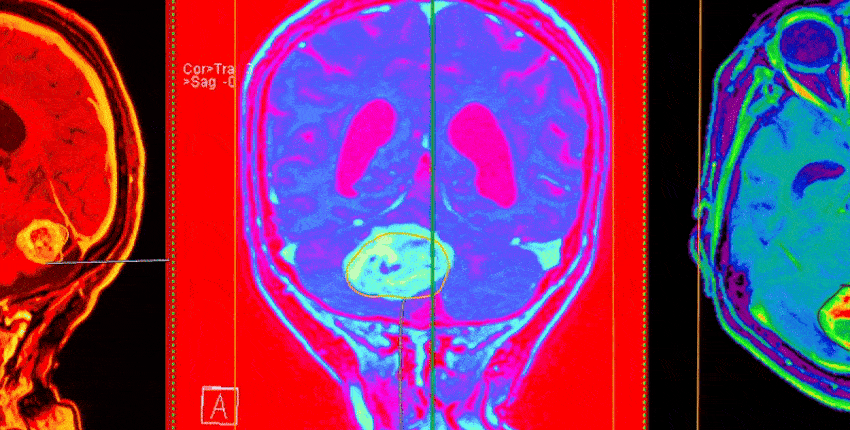

AI Tool Revolutionizes Brain Cancer Diagnosis During Surgery

Image: burhan oral gudu/Getty Images

A research team led by Harvard Medical School has created a groundbreaking AI tool that can accurately differentiate between two types of brain cancer that often look identical under a microscope but require vastly different treatments.

The tool, named PICTURE (Pathology Image Characterization Tool with Uncertainty-aware Rapid Evaluations), has demonstrated near-perfect accuracy in telling apart glioblastoma and primary central nervous system lymphoma (PCNSL). Glioblastoma is the most common and aggressive type of brain tumor, originating from brain cells. In contrast, PCNSL is a rarer cancer that develops from immune cells. Their microscopic similarities frequently lead to misdiagnosis, which can have severe consequences for patient care.